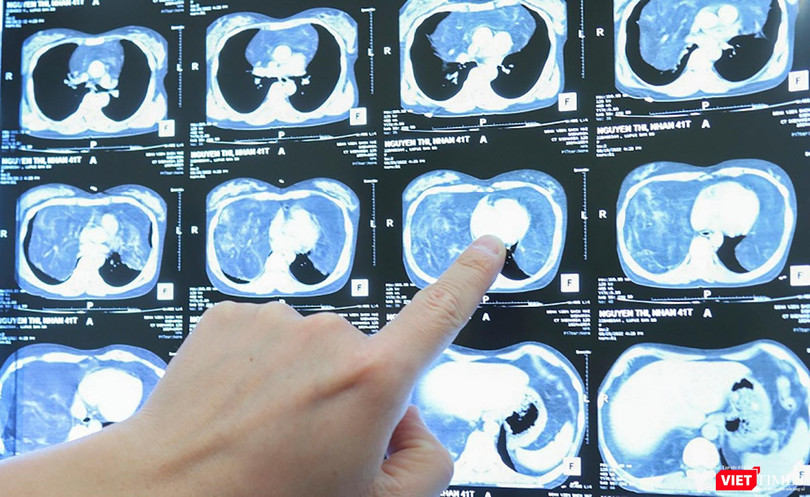

Gần đây, bệnh nhân bị đau tức ngực, khó thở nhiều, triệu chứng ngày càng nặng nên đã đến bệnh viện để kiểm tra. Qua chẩn đoán hình ảnh, các bác sĩ phát hiện bệnh nhân có khối u trung thất lớn, trọng lượng khoảng 4 kg, chiếm phần lớn thể tích lồng ngực. Khối u lớn làm giảm thể tích trường phổi hai bên, gây chèn ép tim và các mạch máu lớn trên nền bệnh lý mãn tính gây không ít lo ngại cho quá trình điều trị.

ThS.Bs. Ngô Gia Khánh - người trực tiếp phẫu thuật cho bệnh nhân - cho biết, khối u là tổ chức mỡ, chiếm toàn bộ trung thất và phần dưới khoang màng phổi, ranh giới u tương đối rõ với các tổ chức xung quanh. Khối u khổng lồ khiến hai phổi của bệnh nhân bị đẩy lên trên, ôm quanh tim và các mạch máu lớn, là nguyên nhân dẫn đến việc bệnh nhân bị tức ngực, khó thở.